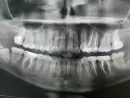

Зуба мудрости во рту нет, десна бледно розовая, во рту проблем нет. Но появились боли, уже месяц в области 6 и 7 зуба внизу справа, то верхние зубы справа (проверила, они здоровы). Также боли у уха, под глазом, щека, в шее от мочки и вниз. Обошла всех врачей, никто не знает отчего. Думала на зуб мудрости, но говорят, что с ним можно жить всю жизнь т.к. он ретинированный и ничем не грозит. Уезжаю на море, на все лето, боюсь, чтобы не заболели зубы от жары. Направила Вам снимки: первый снимок годовалой давности, далее КТ и ортопант - они сделаны только сейчас.

Есть ли какие то изменения на снимках? Есть ли какие то изменения с зубом мудрости? Можно ли данный зуб мудрости не удалять?

Рекомендуем вам обратиться на прием к стоматологу-хирургу. Восьмой зуб расположен таким образом, что никогда полноценно в зубной ряд не прорежется. Но так как он сохраняет тенденцию к прорезыванию, то будет вызывать боль, сдавливая окружающие ткани, а так же гипертонус мышц. Как правило, такие зубы рекомендуется удалить.